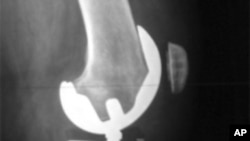

X光照射显示人工的膝关节

数百万的美国人患有骨关节炎,又称退化性关节疾病。病情严重的需要做人工关节替换手术。人工关节可能是用合金、塑料和陶瓷制成的。不过,新的研究显示,利用病人自己的干细胞,有可能修复受损的关节。

骨关节炎通常使用止痛剂和消炎药治疗。但是病情严重时,可以考虑用人工关节替换受损的关节。不过,这种选择并不适于人数越来越多的年轻患者。

哥伦比亚大学医学中心的杰里米·毛说:“金属关节的平均使用寿命是10年到15年。因此可以想见,如果你只有50岁、55岁,甚至更年轻的话,外科医生可能不愿意为你换金属关节,因为他知道,过10到15年,人工关节可能就不能用了。”